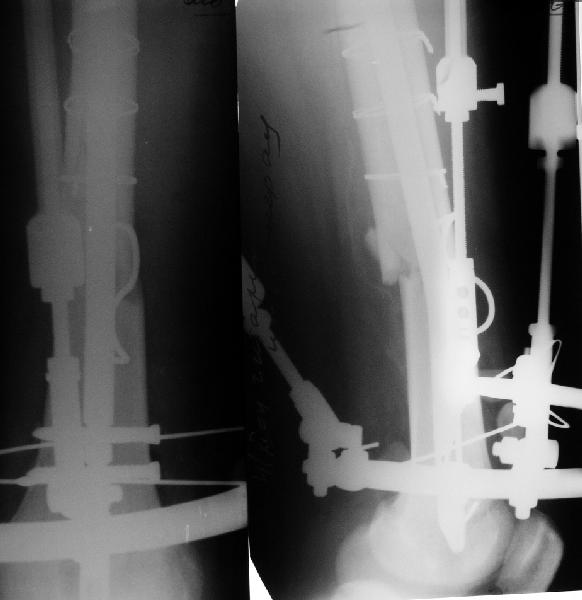

Просьба простить за длительное молчание, не было фотоаппарата, чтобы перенести рентгенограммы. Больного прооперировали в прошлый четверг, как и предполагали, голень проблем не доставила(настолько, что даже не ввели дистальные винты по ряду причин: срок после травмы, целая малоберцовая, последующая длительная ходьба без нагрузки, да и гвоздь сел плотно). Изначально планировали после удаления фиксатора антеградно завести стержень и утопить конец, но вопрос был исчерпан, когда выяснилось, что все имеющиеся стержни слишком длинные, пришлось ретроградно забить большеберцовый гвоздь, после рассверливания; серьезные проблемы возникли с устранением ротации. В вертельной области сломали стержень-джойстик(привет установщику эндопротеза), дальнейшие манипуляции проводили пучком спиц и стержнем с кондуктором. Закончили все аппаратом таз-бедро. Решили что возможные огрехи с ротацией устраним после открытого вправления. Снимки прилагаю. Спасибо за участие в обсуждении. Обязуюсь информировать о дальнейших этапах лечения.